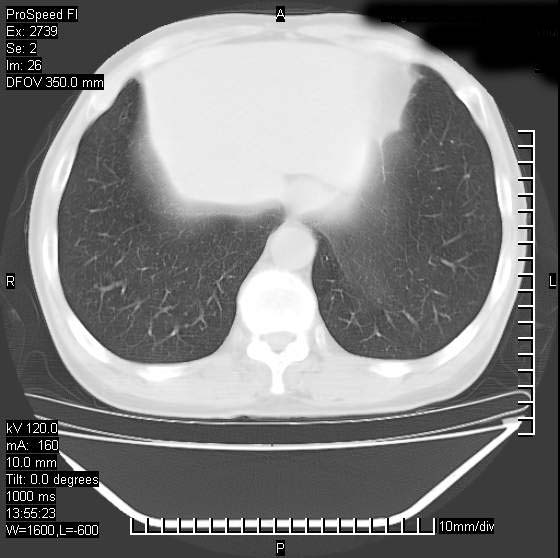

以下是引用andymaomao在2007-12-7 15:54:00的发言:[br]1.双上肺陈旧肺tb灶;[br]2.双中上肺矽肺;[br]3.双肺气肿;[br]4.图中箭头所指乃下腔静脉。

以下是引用山之魂海之韵在2007-12-7 18:59:00的发言:[br]支持矽肺,左肺上叶陈旧性结核,肺气肿。箭头所指乃下腔静脉。下腔静脉显影比主动脉显影迟,增强动脉后迟可以是不均匀的。

以下是引用chengjiaqiu1在2007-12-7 17:49:00的发言:[br]矽肺,左肺上叶陈旧性结核,肺气肿。中箭头所指乃下腔静脉。